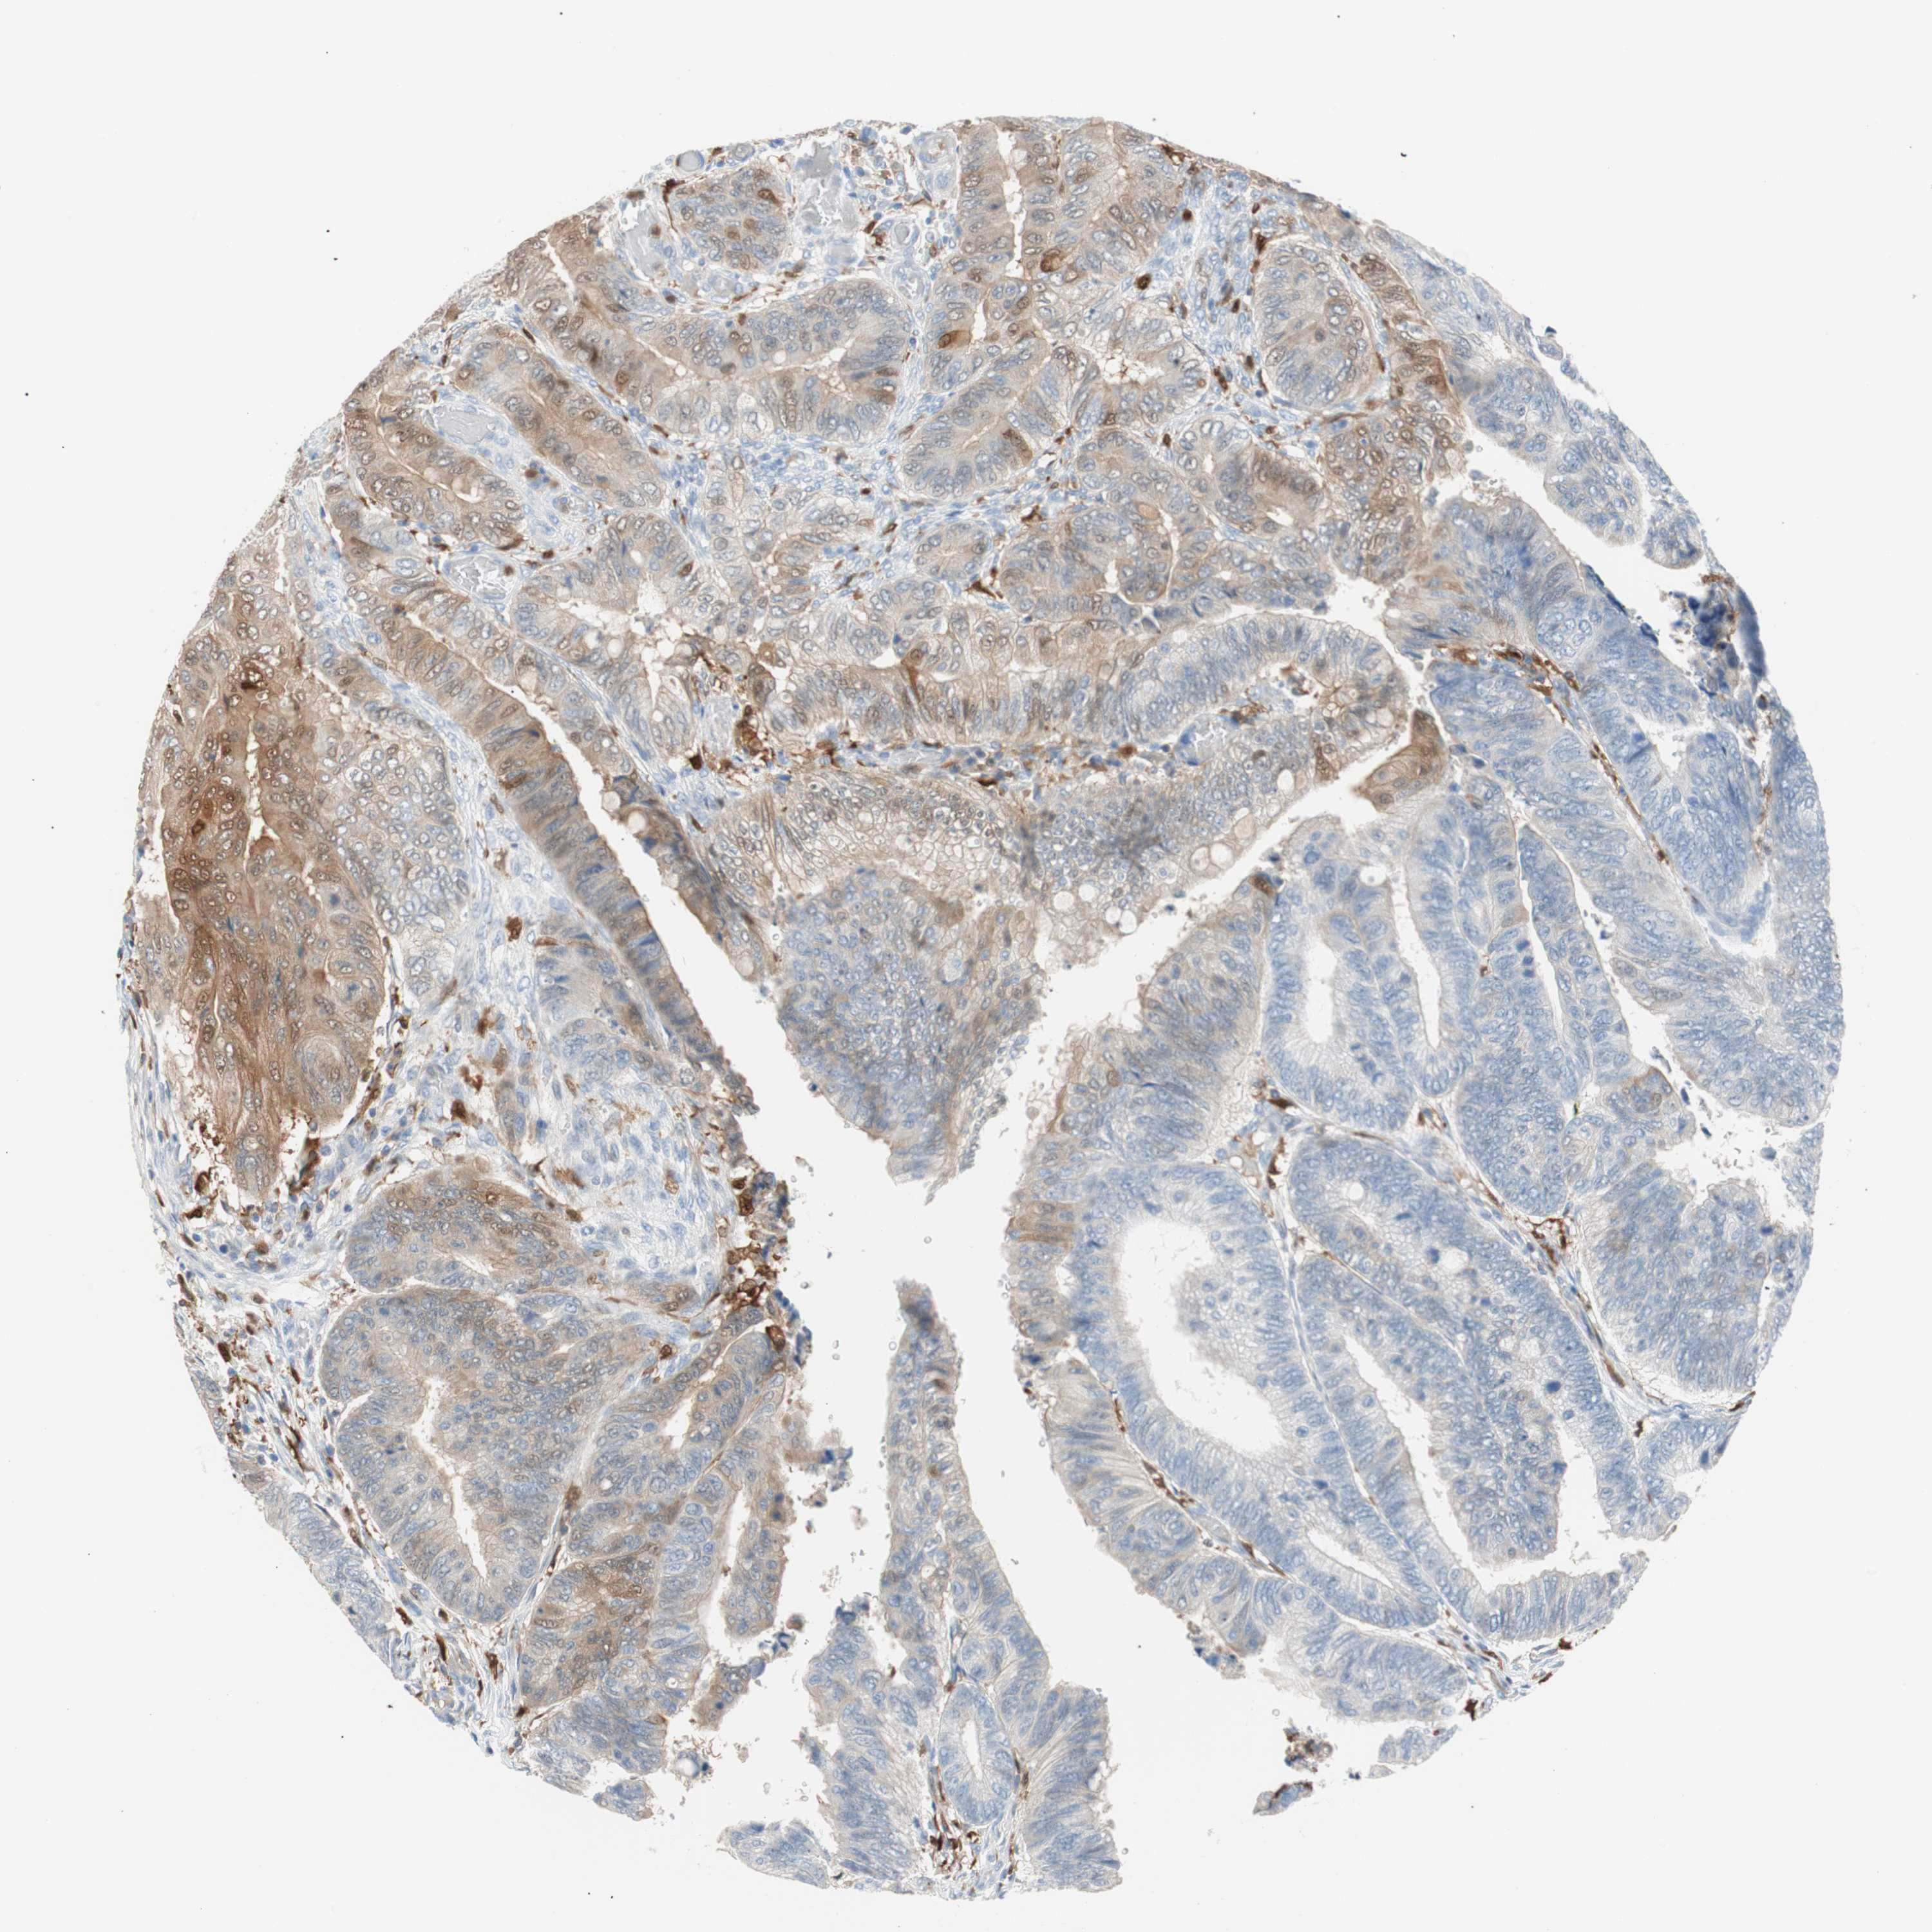

Colorectal cancer

Colon adenocarcinoma